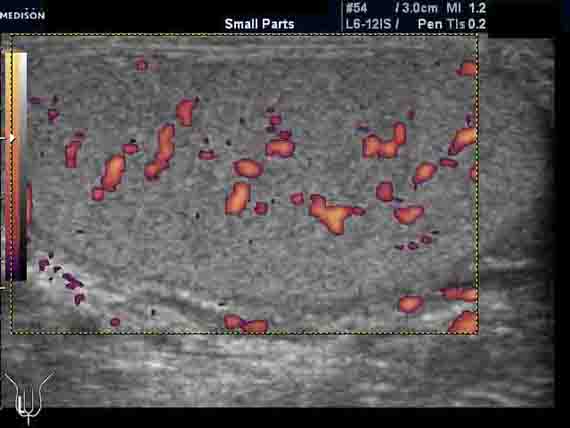

Пациент 42 лет. Направлен на УЗИ мошонки с подозрением на небольшую кисту в придатке яичка. Жалоб нет. Анамнез без особенностей. Пальпаторно мошонка в норме.

При УЗИ киста не обнаружена. Выявляются небольшая неоднородность структуры яичек (изменения незначительные) и заметное усиление сосудистого рисунка (до 11-12 срезов сосудов в скане). Другой патологии нет. Форма и размеры яичек нормальные. Придатки яичек не изменены. Признаков гидроцеле и ваникоцеле нет.

Вопрос: в чем причина заметного усиления сосудистого рисунка яичек?